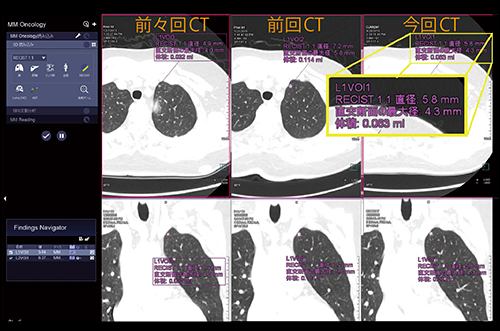

肺結節を自動的に同定する読影支援機能である“CT Lung CARE”は,画面上の“Lung CAD”というボタンをクリックすると,2,3mmの小さな肺結節まで高精度に自動検出するアプリケーションである。CT Lung CAREは経時的な評価にも有用で,過去の検査画像をあらかじめsyngo.viaに読み込んでおけば自動的に結節を検出・計測して最新の画像と比較できる(図7)。さらに,「RECISTガイドライン」に対応したグラフ表示により,治療効果判定も行える。

図7 CT Lung CAREを用いた肺結節の経時的評価